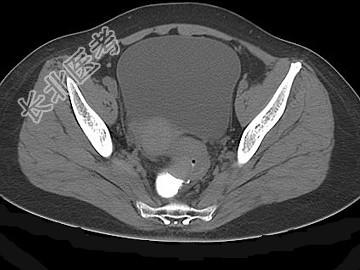

- 单项选择题女,67岁, 排便习惯改变,血便3月入院, CT检查如图所示,下列说法错误的是 ( )

A、直肠肠腔局限性增厚

B、其表面欠光整,边界欠清晰

C、可做直肠指检及活检以确定病变性质

D、此为直肠息肉

E、此为直肠癌